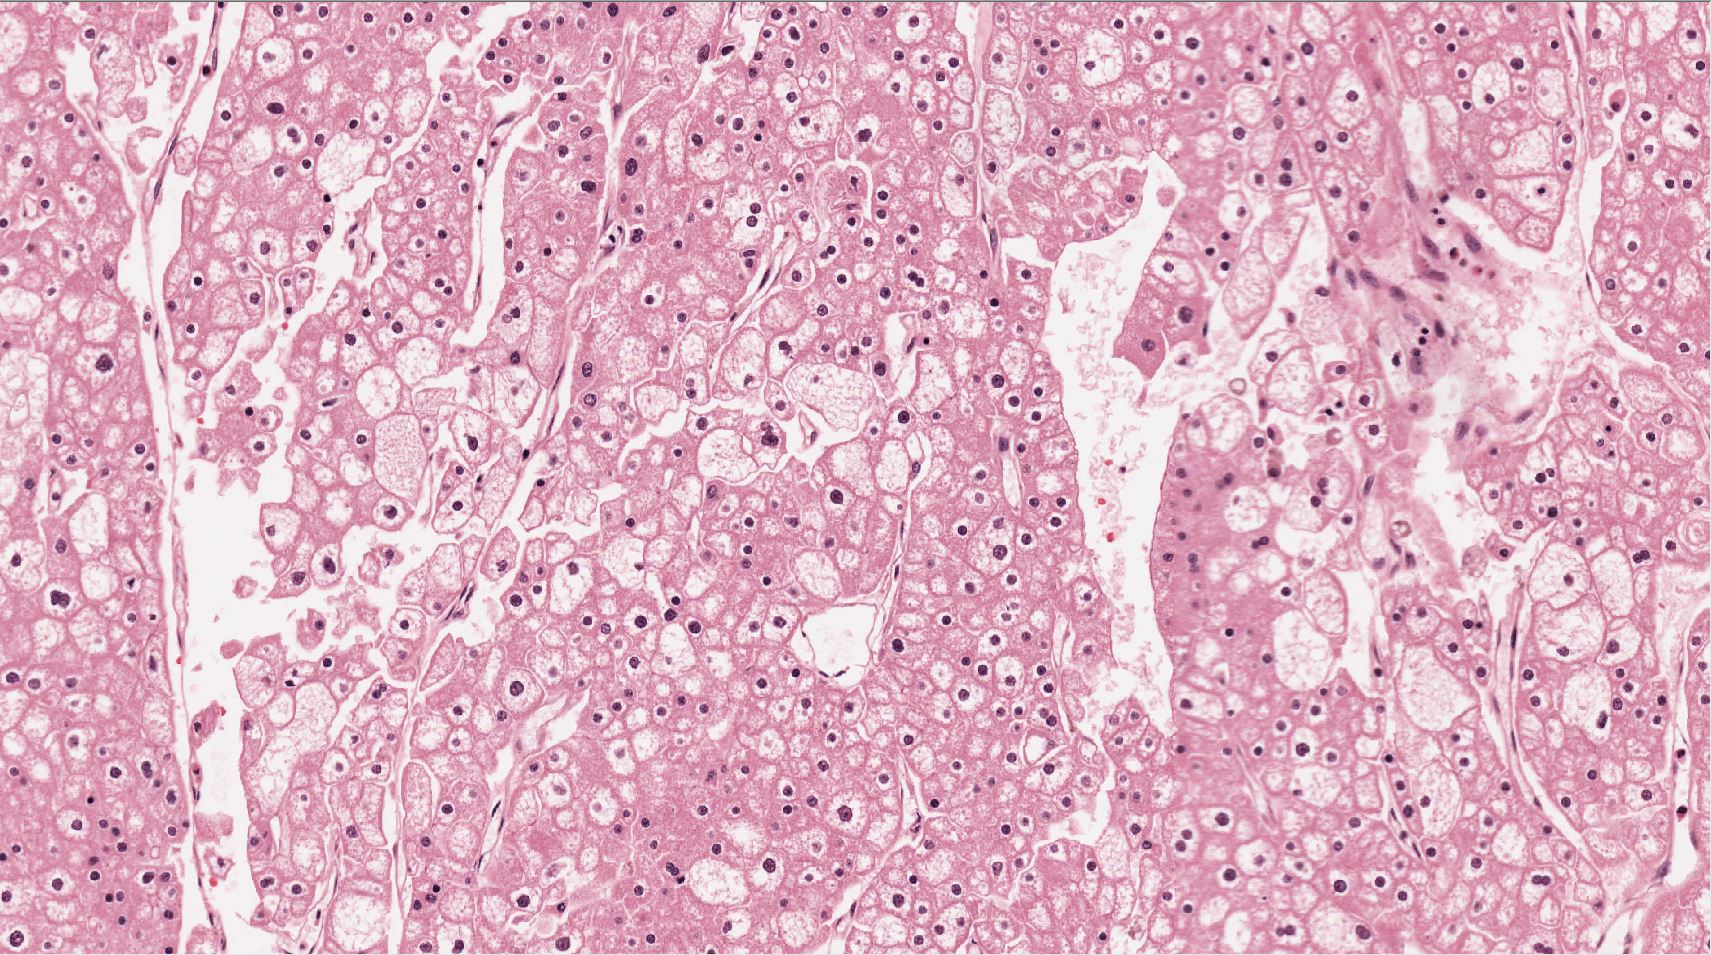

Renal tumor grading

Case ID: 544